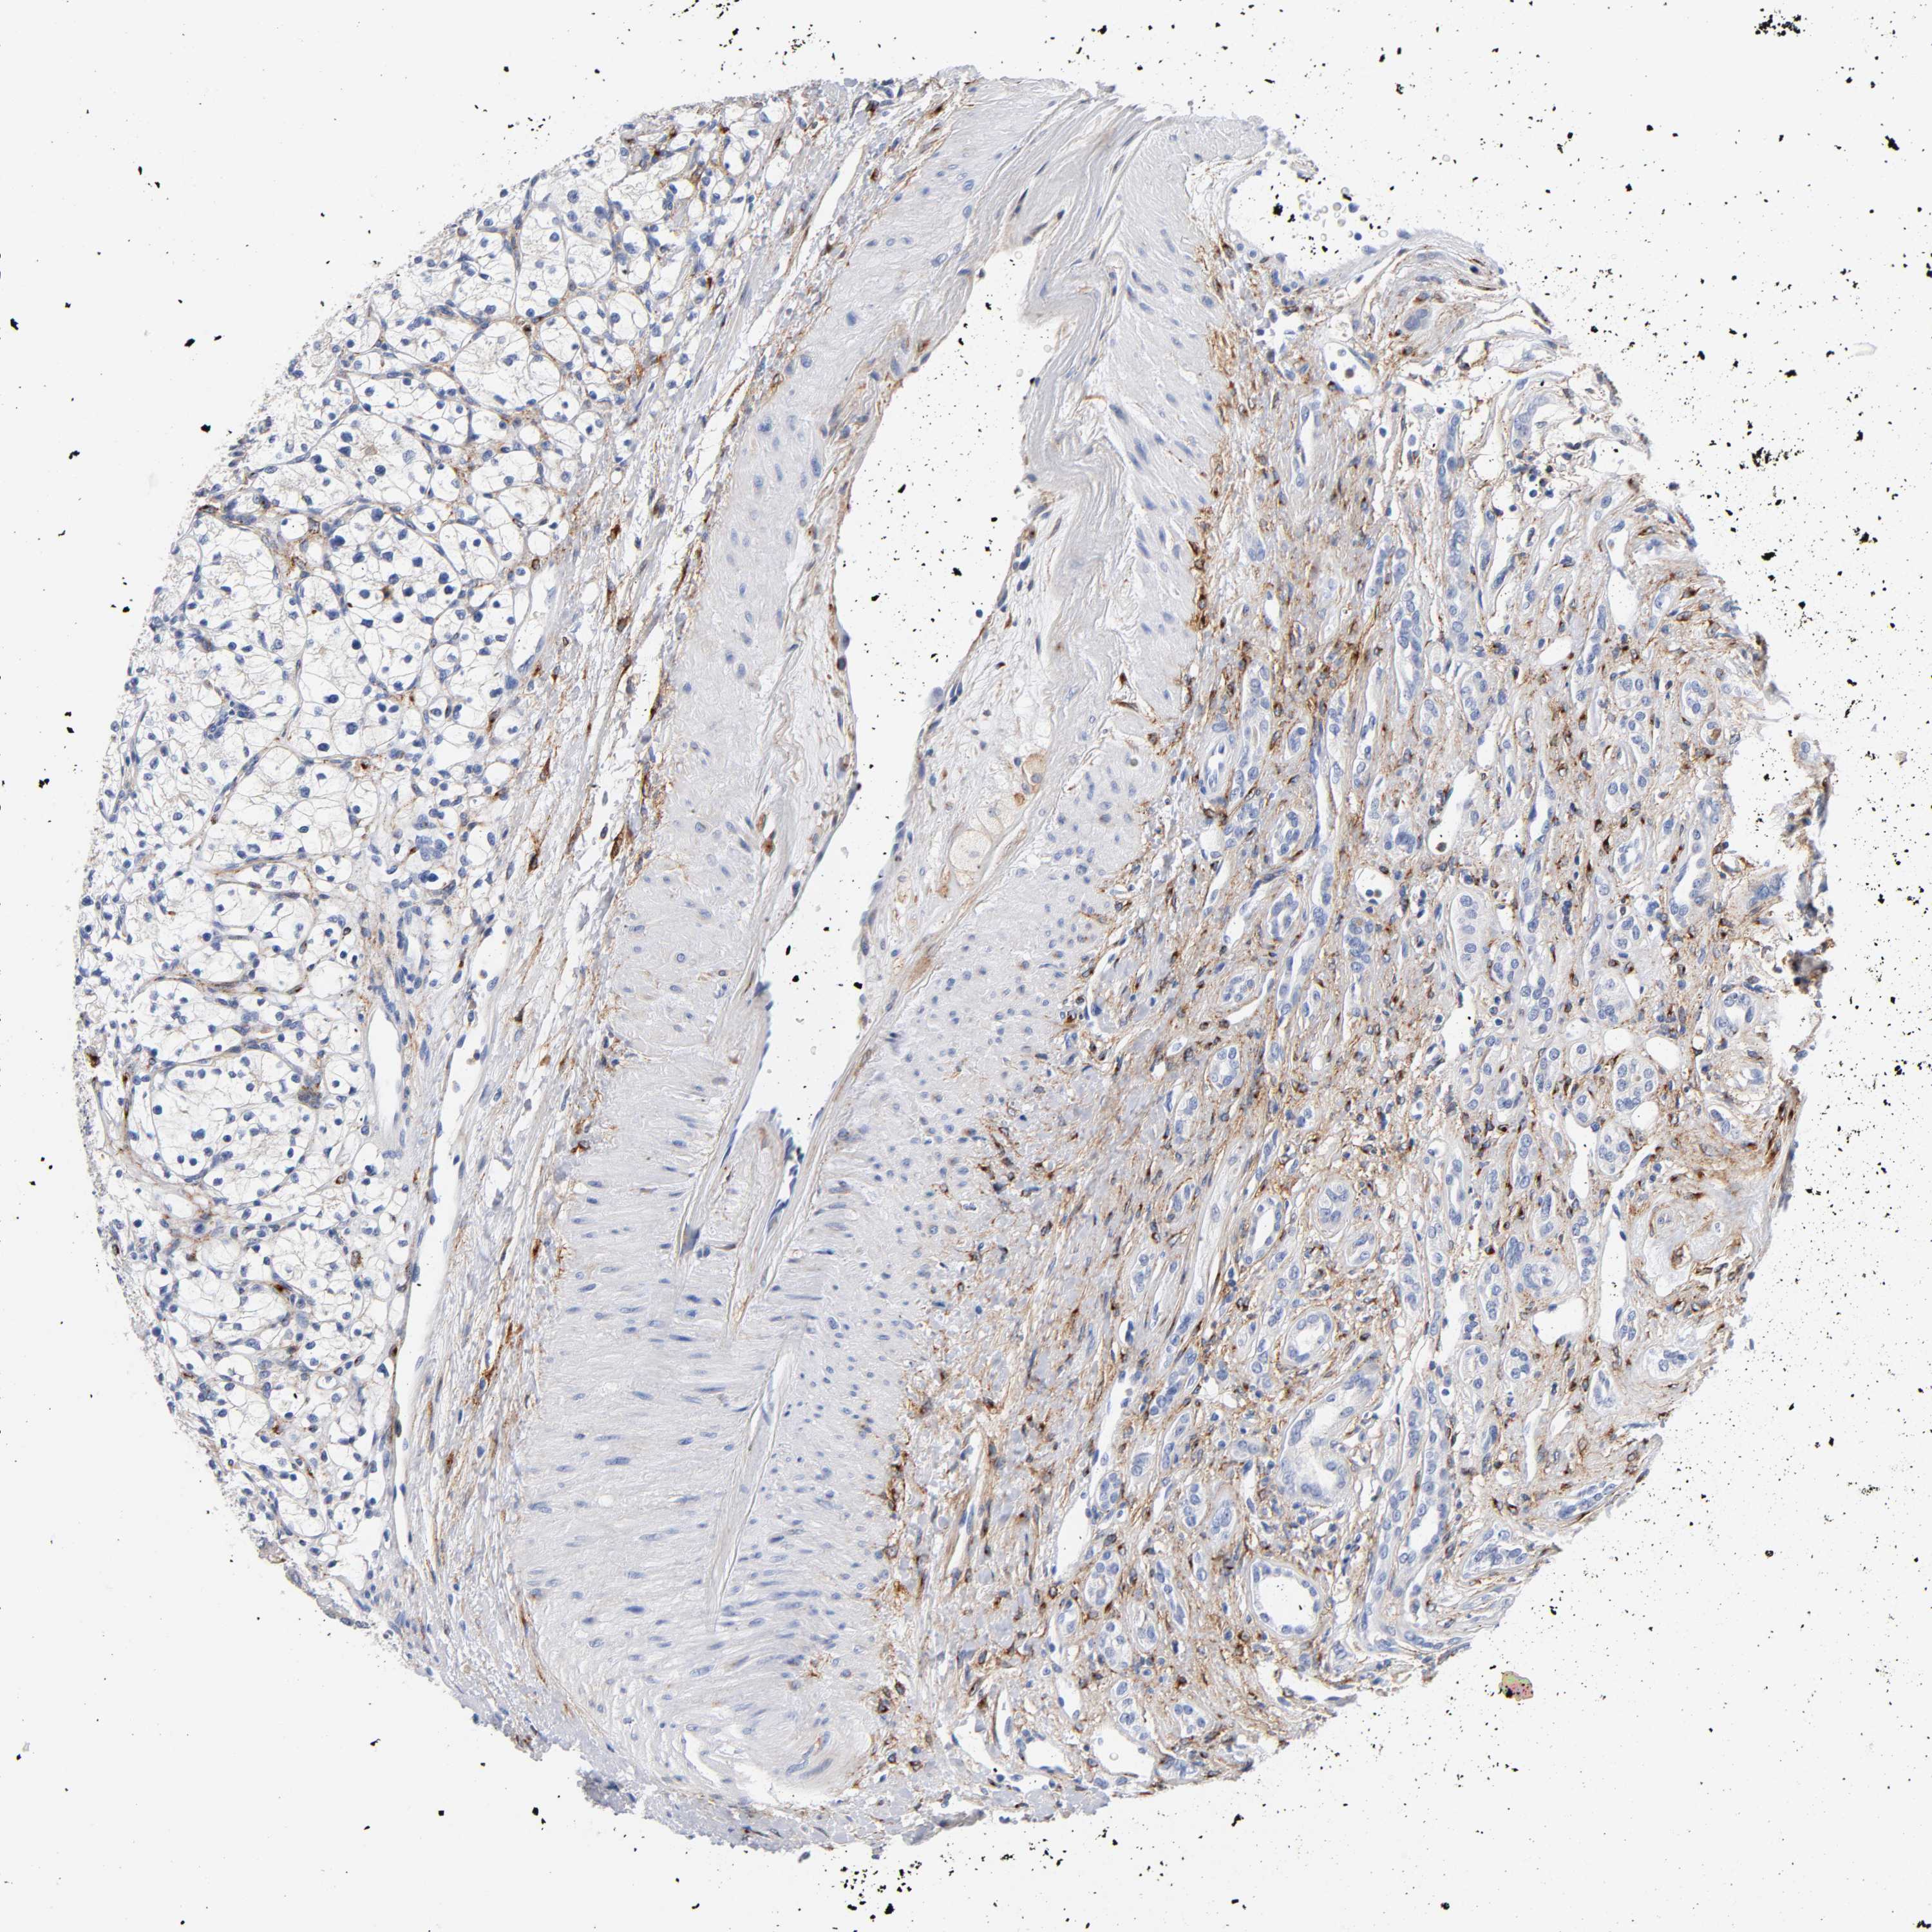

KIDNEY RENAL CLEAR CELL CARCINOMA (VALIDATION) - Interactive survival scatter ploti

The Survival Scatter plot shows the clinical status (i.e. dead or alive) for all individuals in the patient cohort, based on the same data that underlies the corresponding Kaplan-Meier plots. Patients that are alive at last time for follow-up are shown in blue and patients who have died during the study are shown in red.

The x-axis shows the expression levels (FPKM) of the investigated gene in the tumor tissue at the time of diagnosis. The y-axis shows the follow-up time after diagnosis (years). Both axes are complimented with kernel density curves demonstrating the data density over the axes. The top density plot shows the expression levels (FPKM) distribution among dead (red) and alive patients (blue). The right density plot shows the data density of the survived years of dead patients with high and low expression levels respectively, stratified using the cutoff indicated by the vertical dashed line through the Survival Scatter plot. This cutoff is automatically defined based on the FPKM cutoff that minimizes the p-score. The cutoff can be changed by dragging the vertical line or by entering a cutoff value in the square labeled "Current cut-off".

Under the Survival Scatter plot the p-score landscape (black curve; left axis) is shown together with dead median separation (red curve; right axis). Dead median separation is the difference in median mRNA expression between patients who have died with high and low expression, respectively. It is calculated as follows: median FPKM expression of dead patients with high expression - median FPKM expression of dead patients with low expression. This is intended to aid the user in visually exploring custom cutoffs and the associated p-scores and dead median separation.

Individual patient data is displayed and can be filtered by clicking on one or more of the category buttons on the top of the page. Categories describing expression level and patient information include: high, low, alive, dead, female, male and tumor stages. The scale of the x-axis can be toggled between linear and log-scale by clicking on the "x log" button. Mouse-over function shows TCGA ID, patient information and mRNA expression (FPKM) for each patient.

& Survival analysisi

Kaplan-Meier plots summarize results from analysis of correlation between mRNA expression level and patient survival. Patients were divided based on level of expression into one of the two groups "low" (under cut off) or "high" (over cut off). X-axis shows time for survival (years) and y-axis shows the probability of survival, where 1.0 corresponds to 100 percent.

LRP1 is not prognostic in Kidney Renal Clear Cell Carcinoma (validation)

Best expression cut offi

Based on the FPKM value of each gene, patients were classified into two groups and association between prognosis (survival) and gene expression (FPKM) was examined. The best expression cut-off refers the FPKM value that yields maximal difference with regard to survival between the two groups at the lowest log-rank P-value. Best expression cut-off was selected based on survival analysis .

When clicking on this number, the vertical dashed line indicating cut-off, the interactive survival plot, and the Kaplan-Meier curve will be adjusted to show results based on the best expression cut-off.

: 43.86

TCGA RNA samplesi

RNA-seq data is reported as average FPKM (number Fragments Per Kilobase of exon per Million reads), generated by the The Cancer Genome Atlas (TCGA) .

Normal distribution across the dataset is visualized with box plots, shown as median and 25th and 75th percentiles. Points are displayed as outliers if they are above or below 1.5 times the interquartile range. FPKM values of the individual samples are presented next to the box plot.

Average pTPM 32.0

Number of samples 100